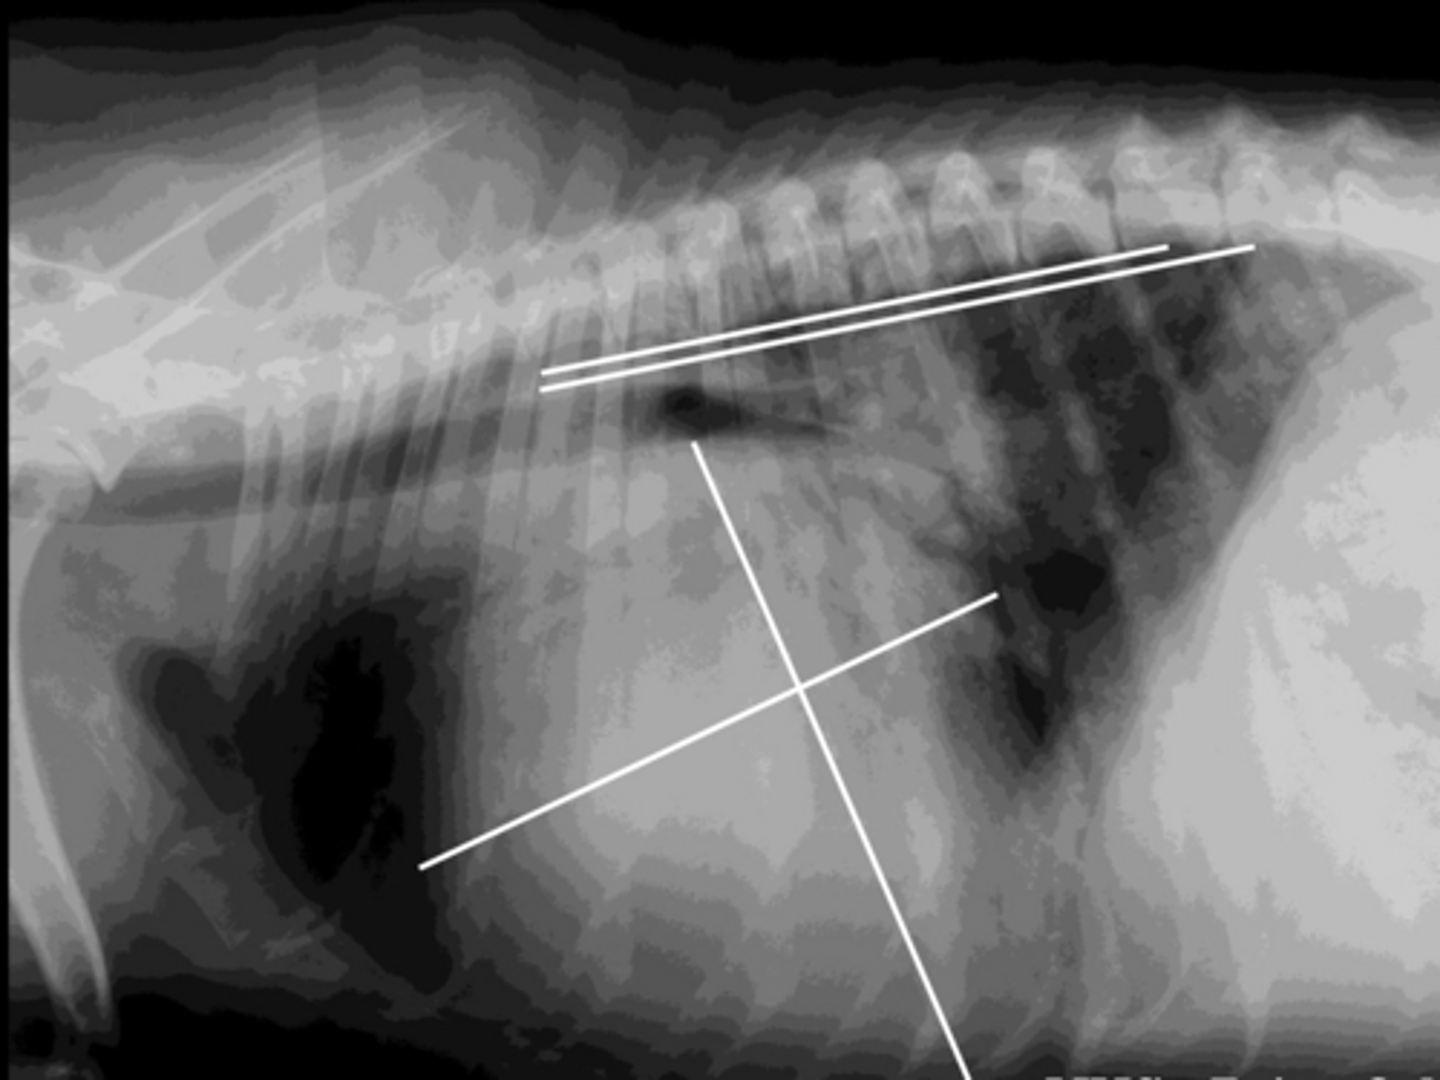

DCM

-stage c

- Interstitial lung pattern suggest CHF

What is your dx?